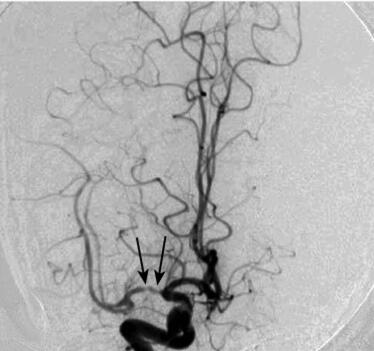

辅助检查:DSA(2011年6月2日):右侧大脑中动脉分叉前弥漫变细伴狭窄65%(图1),前向血流2级,右侧C4段斑块形成,右侧大脑前动脉缺如,右侧后交通动脉乳头状扩张,右颈总动脉分叉处斑块形成;左侧颈外动脉开口斑块形成,左侧颈内动脉C4、C6、C7段斑块形成,左侧椎动脉V1、V3段斑块形成,右侧椎动脉止于右侧小脑后下动脉,其余血管未见异常。

图1 术前DSA结果:右侧大脑中动脉分叉前弥漫变细伴狭窄(箭头)